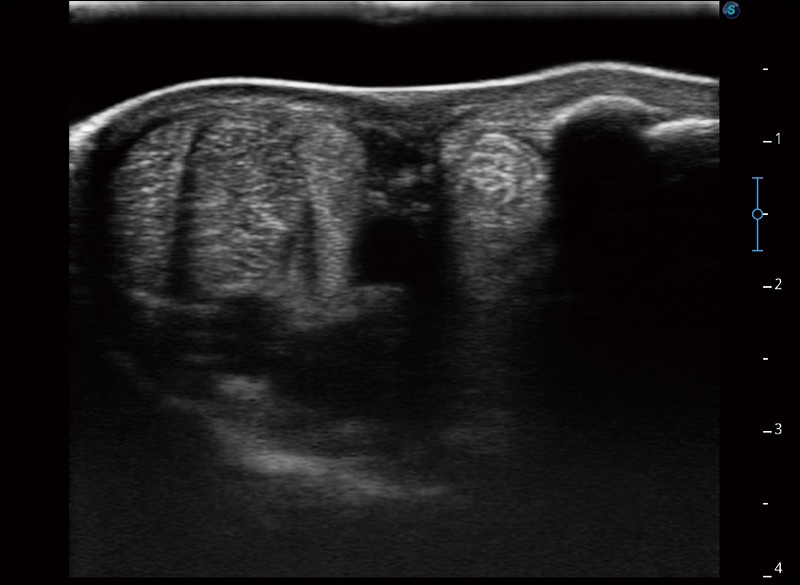

任意波束合成技术

在不牺牲时间分辨率的情况下提供出色的图像

空间复合成像

优化不同角度的图像

实时宽景成像

可实时观察感兴趣区域和病变位置